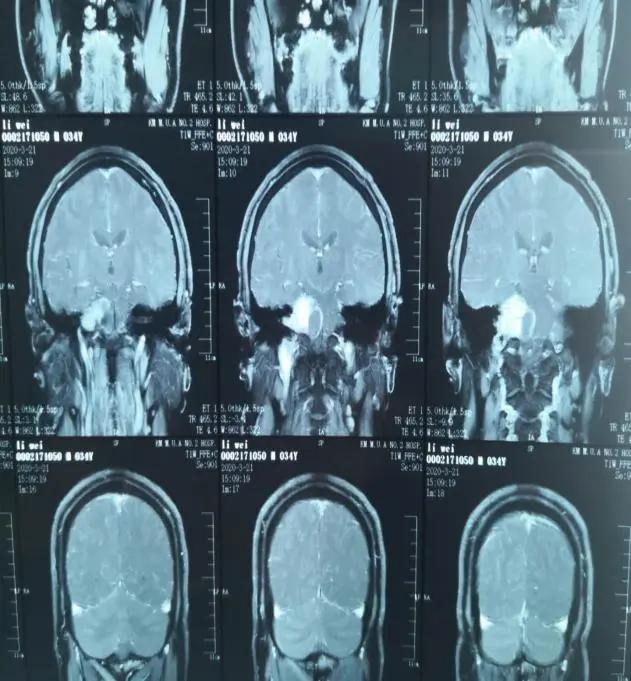

图一术前颅脑增强核磁扫描显示右侧桥小脑角区占位

随后,李先生来到云南省中医医院/云南中医药大学第一附属医院外科,入院后行颅脑核磁平扫+增强扫描提示:右侧内耳道扩大,其内可见一大小约3.8cm*3.5cm的囊实性结节影(图一)。